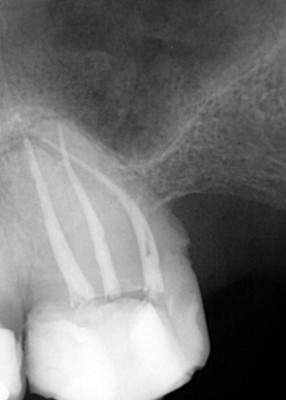

Udrożnienie kanału, w którym zostało złamane narzędzie pozwala wypełnić poprawnie kanały zęba i zachować go z dobrym rokowaniem na kolejne lata.

Usuwanie złamanych narzędzi w powiększeniu oraz opracowywanie trudnych anatomicznie kanałów zębów, które odbywa się pod mikroskopem i jest gwarancją, że leczenie będzie przeprowadzone poprawnie.